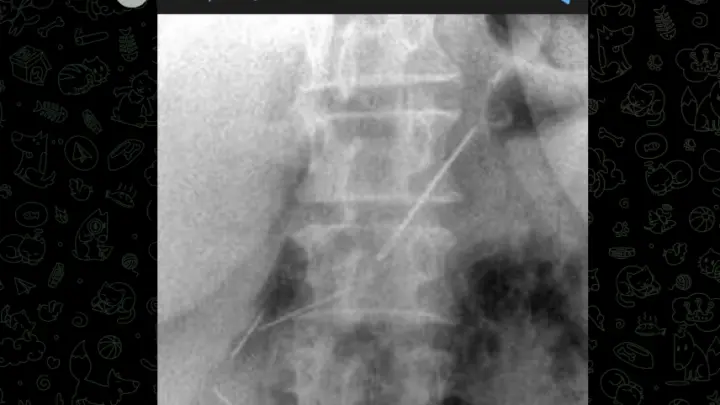

Месяц в животе: в Подмосковье врачи достали из женщины 4 швейные иглы

Женщина каким-то образом проглотила их и забыла об этом.

В Красногорскую больницу обратилась 59-летняя женщина с болями в животе. Врачи сделали диагностику и обалдели: в брюшной полости пациентки торчат три швейные иглы, еще одна застряла в передней брюшной стенке. Самое удивительное - женщина проглотила их примерно месяц назад и все это время как-то жила с этим.

За месяц иглы успели врасти в ткани, что превратило операцию в ювелирную работу. Хирургам пришлось делать лапаротомию - разрезать брюшную стенку, чтобы добраться до инородных тел. В итоге все четыре иглы достали. Одна из них прошла через стенку желудка и воткнулась в поджелудочную железу. Повезло, что железу удалось сохранить.

Заведующий отделением Николай Мурашов говорит, что случай уникальный. Обычно с такими вещами тянуть нельзя - иглы мигрируют по организму и могут продырявить что угодно. Но здесь, видимо, звезды сошлись. Пациентка сейчас восстанавливается.